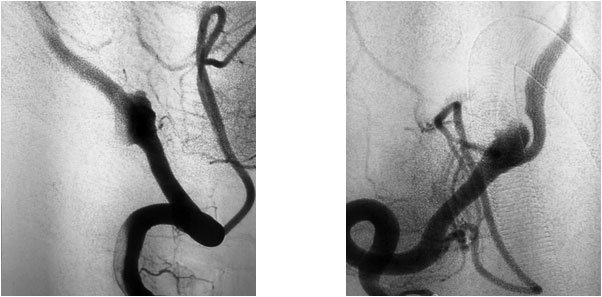

患者为65岁男性,20天前无明显诱因突然出现四肢无力,呈渐进性加重,以下肢为甚,伴头晕、头痛,呈一过性,在当地医院急查头颅CT示:右侧椎动脉V4段动脉瘤。当时症状自行缓解,未做处理。后患者自感症状间断发生,为求进一步治疗,遂转至上海蓝十字脑科医院。

患者既往有“高血压”病史8年,“糖尿病”病史1年余。头颅增强CTA示:右侧椎动脉V4段动脉瘤,直径7.5毫米,右侧颈内动脉C4-6段多发钙化斑块形成,伴相应管腔轻度狭窄,左侧颈内动脉C5-6段微钙化斑块形成,左侧椎动脉偏细。

张琪博士指出,患者动脉瘤虽未破裂但已压迫大脑周围神经,导致头晕、头痛及四肢无力等神经系统症状和体征,手术指征明显。

在充分准备后,张琪博士在刘春医生、周林华医生协助下为患者进行了支架辅助动脉瘤栓塞手术。填入弹簧圈后,再置入支架,完全释放后,造影显示动脉瘤无显影,支架覆盖良好,载瘤动脉通畅,撤出微导管输送系统,复查双侧椎动脉造影显示远端血流通畅。

▲ 术前影像

▲ 术后,造影显示动脉瘤无显影,栓塞成功